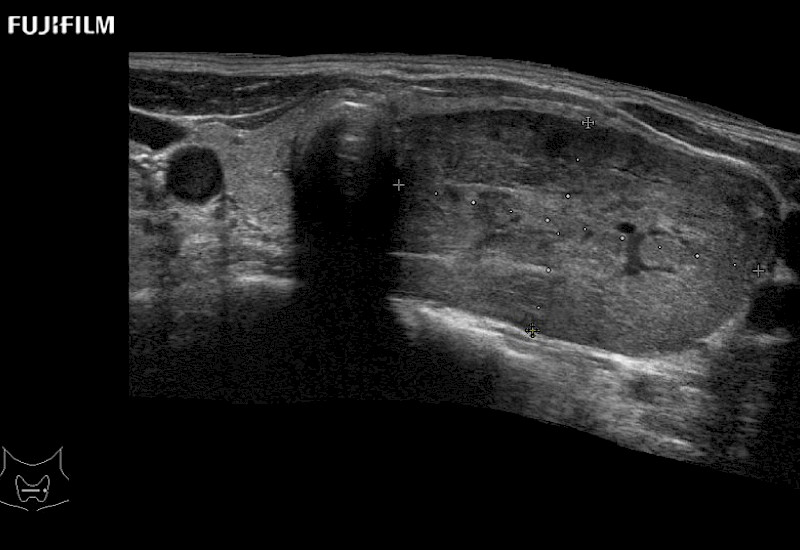

Extraordinary high-resolution digital imaging

- Instant feedback on tumor margin delineation

- Valuable information to guide tumor resections

- Instant feedback on tumor margin delineation

- Instant feedback on tumor margin delineation

- Instant feedback on tumor margin delineation

- Valuable information to guide tumor resections

- Instant feedback on tumor margin delineation

- Valuable information to guide tumor resections

- Instant feedback on tumor margin delineation

- Valuable information to guide tumor resections

- Instant feedback on tumor margin delineation